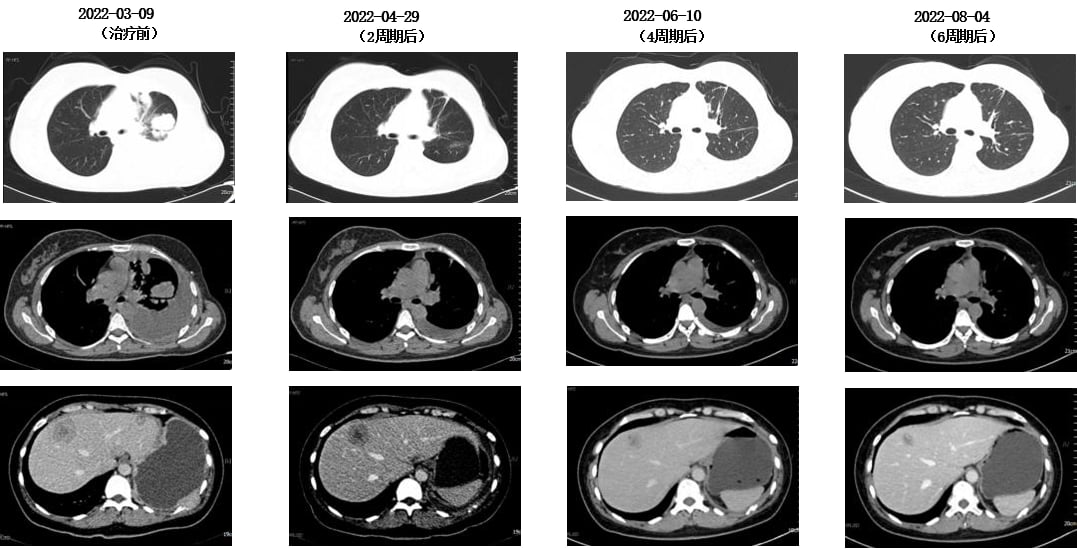

在无进展生存(PFS)长达6年8个月后,2022年2月,患者再次出现胸闷、气短、乏力等症状。影像学检查显示,疾病进展为肝、骨、肺、胸膜、脑多发转移,并伴有左侧胸腔积液。肝穿刺活检病理证实为转移性低分化腺癌,免疫组化提示ER高表达,HER2(2+),FISH检测显示HER2扩增,再次明确为HER2阳性乳腺癌。

此时,曲妥珠单抗(一种经典的HER2靶向药)已纳入医保,为患者带来了新的希望。MDT讨论后,患者接受了以下解救治疗:

- 靶向联合化疗:TCbH方案(曲妥珠单抗+白蛋白结合型紫杉醇+卡铂)4周期,随后TH方案(曲妥珠单抗+白蛋白结合型紫杉醇)2周期。

- 骨转移治疗:定期静脉注射唑来膦酸,并口服碳酸钙D3片和骨化三醇进行补钙。

令人惊喜的是,治疗后患者疗效评价为部分缓解(PR),特别是颅内病灶达到了完全缓解(CR),且长期无症状。这充分证明了HER2靶向治疗的强大效果,即使是脑转移这种棘手的情况,全身治疗也能取得显著成效。随后,患者进入维持治疗阶段,使用氟维司群+曲妥珠单抗+戈舍瑞林,病情持续稳定。